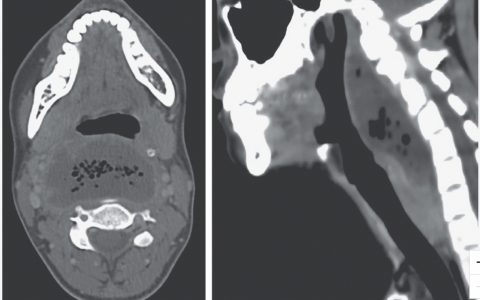

A 73-year-old woman had sudden chest pain during pulmonary-function testing. She had a history of breast cancer, for which a double mastectomy with breast reconstruction had been performed 23 years earlier, followed by the insertion of silicone breast implants 12 years later. She also had a history of non–small-cell lung cancer, for which a superior segmentectomy of the right lower lung had been performed by means of open thoracotomy 3 years before presentation. To evaluate the patient’s chest pain, a computed tomographic scan of the chest was performed. What radiographic finding is shown?

胸部的CT扫描显示右侧乳房假体移位到下胸膜腔内。胸内迁移是乳房植入术极其罕见的并发症。这种情况通常由于肋间肌肉和筋膜的弱点发生,往往与之前的心脏和胸部手术有关。在随后的右侧开胸手术中,乳房假体被取出,胸壁缺陷被重建,她的咳嗽症状后来缓解了。

正确答案:A